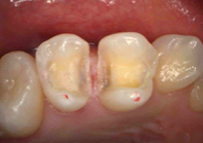

レントゲンでのむし歯のチェックや噛み合わせなどのチェック